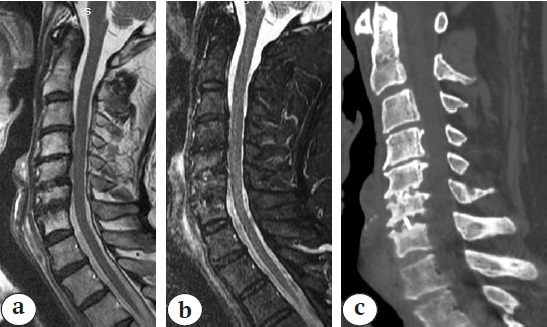

Radiological examination revealed an angular kyphotic deformity of the cervical spine of 48° according to Cobb, cSVA 12 mm, T1S 30° (Fig. 4).

Fig. 4. X–ray (a), CT (b) and MRI (c) at the time of hospital admission: angular kyphosis 48° Cobb, destruction of C3–С5, myelopathy at C2–С3, no signs of active inflammatory process (abscesses)